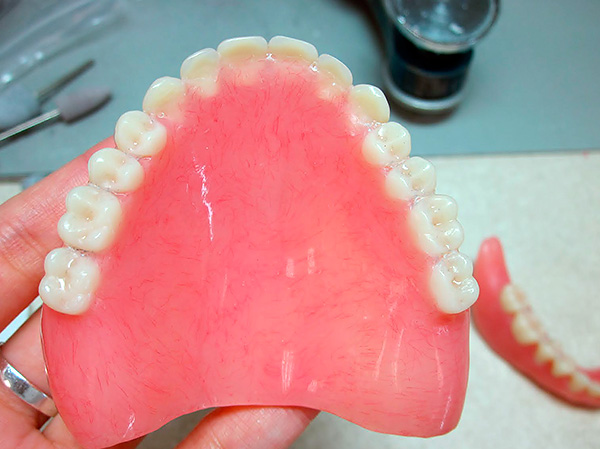

Da mesma forma, é possível instalar uma prótese já nos mini-implantes do paciente se a prótese estiver em boas condições e feita há menos de 2-3 anos. Um sistema de fixação é incorporado a ele antes da operação e é instalado diretamente nos pilares. Depois disso, o paciente pode remover e colocar a prótese para realizar procedimentos de higiene.

Para fixação em mini-implantes, uma prótese antiga pode ser usada se ainda não estiver muito desgastada e fabricada com alta qualidade. Acredita-se que dentaduras acrílicas de 2 a 3 anos com leve desgaste sejam bastante adequadas para fixação. Ao mesmo tempo, a preparação e fixação de uma prótese antiga custa muito menos do que uma nova prótese e leva 2-3 dias no tempo.

Para modificar a prótese antiga, são feitos nele os aprofundamentos dos pilares dos implantes já instalados, estritamente de acordo com sua projeção em uma base plástica, então são instalados acessórios de silicone nesses recessos, e os pilares são inseridos neles, fixando rigidamente a prótese.

Essa tecnologia é boa, em primeiro lugar, pelo baixo custo e, em segundo lugar, pelo uso de uma prótese, à qual o paciente já está acostumado. Mas ela também tem desvantagens. Por exemplo, uma prótese criada inicialmente “para implantes” geralmente possui uma base menos ampla e não tão perceptível. Isto é especialmente verdadeiro para a mandíbula superior: uma prótese fixada em implantes não deve bloquear todo o céu.